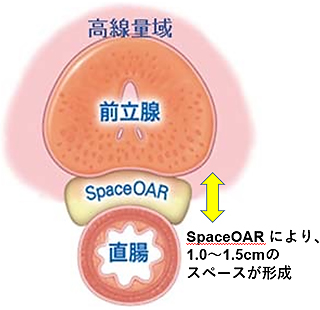

SpaceOAR®システム留置あり

直腸被曝が低減します。

放射線の影響は距離が離れれば低減します。そのため、当院では前立腺と直腸の間にゲル状の物質を挿入し、前立腺と直腸の間を1.0~1.5cm離すことで直腸被曝を低減させる処置として、『直腸周囲ハイドロゲルスペーサ・SpaceOAR®』の留置を行っています。

留置により放射線の直腸への影響が低減され、合併症が減ると考えられます。

ハイドロゲルは注入後、前立腺と直腸の間に約3カ月間スペースを維持し、その後約6カ月かけて体内に吸収されます。